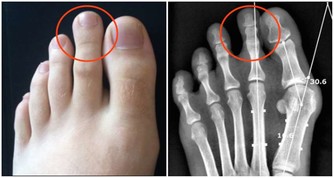

後半夜(3:00~7:00)不睡,NK細胞的活性同樣下降。NK細胞是人體免疫系統裡抗腫瘤、抗病毒的“特種部隊”,它的活性下降了,我們的免疫系統便不再強悍,癌細胞也就有了可乘之機。

此外,缺乏睡眠會導致血壓上升、內分泌和代謝異常、炎症反應炎症物質增多。在之前的課程裡我們已經講解了炎症物質與癌症的關係,過量生產的炎症物質積蓄在體內會誘發、加重癌細胞的生長與擴散,這也是睡眠不足容易引發癌症的原因之一。